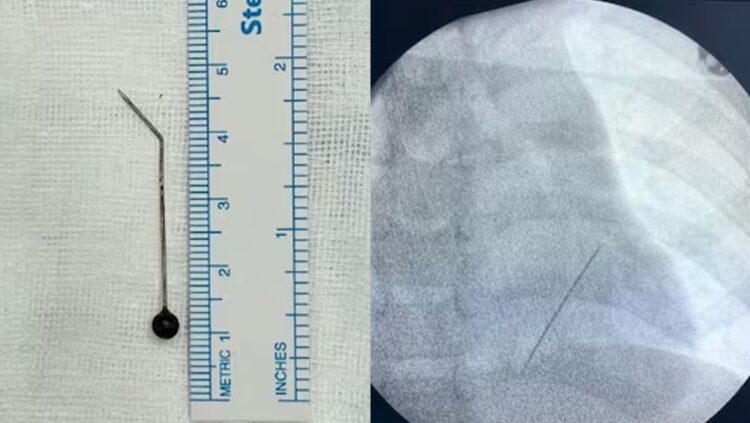

എക്സ്റേയിൽ ഇടതുവശത്തെ ശ്വാസകോശത്തിന്റെ ഏറ്റവും അടിത്തട്ടിൽ ലോവർ ലോബിനോട് ചേർന്ന് പിൻ കിടക്കുന്നതായി കണ്ടെത്തി. ഹൃദയത്തിലേക്കുള്ള പ്രധാന രക്തക്കുഴലുകൾക്ക് അടുത്തായാണ് സൂചി കിടന്നിരുന്നത്. അതിനാൽ തന്നെ അത് പുറത്തെടുക്കുക എന്നത് ശ്രമകരമായിരുന്നു.

കൊച്ചി അമൃത ആശുപത്രിയിൽ ചീഫ് ഇന്റർവെൻഷണൽ പൾമണോളജിസ്റ്റ് ഡോ ടിങ്കു ജോസഫിന്റെ നേതൃത്വത്തിലാണ് കുട്ടിയുടെ ശ്വാസകോശത്തിൽ കുടുങ്ങിയ 5 സെന്റിമീറ്ററോളം നീളമുള്ള സൂചി മൂന്നരമണിക്കൂറോളം നീണ്ട റിജിഡ് ബ്രോങ്കോസ്കോപിയിലൂടെ പുറത്തെടുത്തത്.